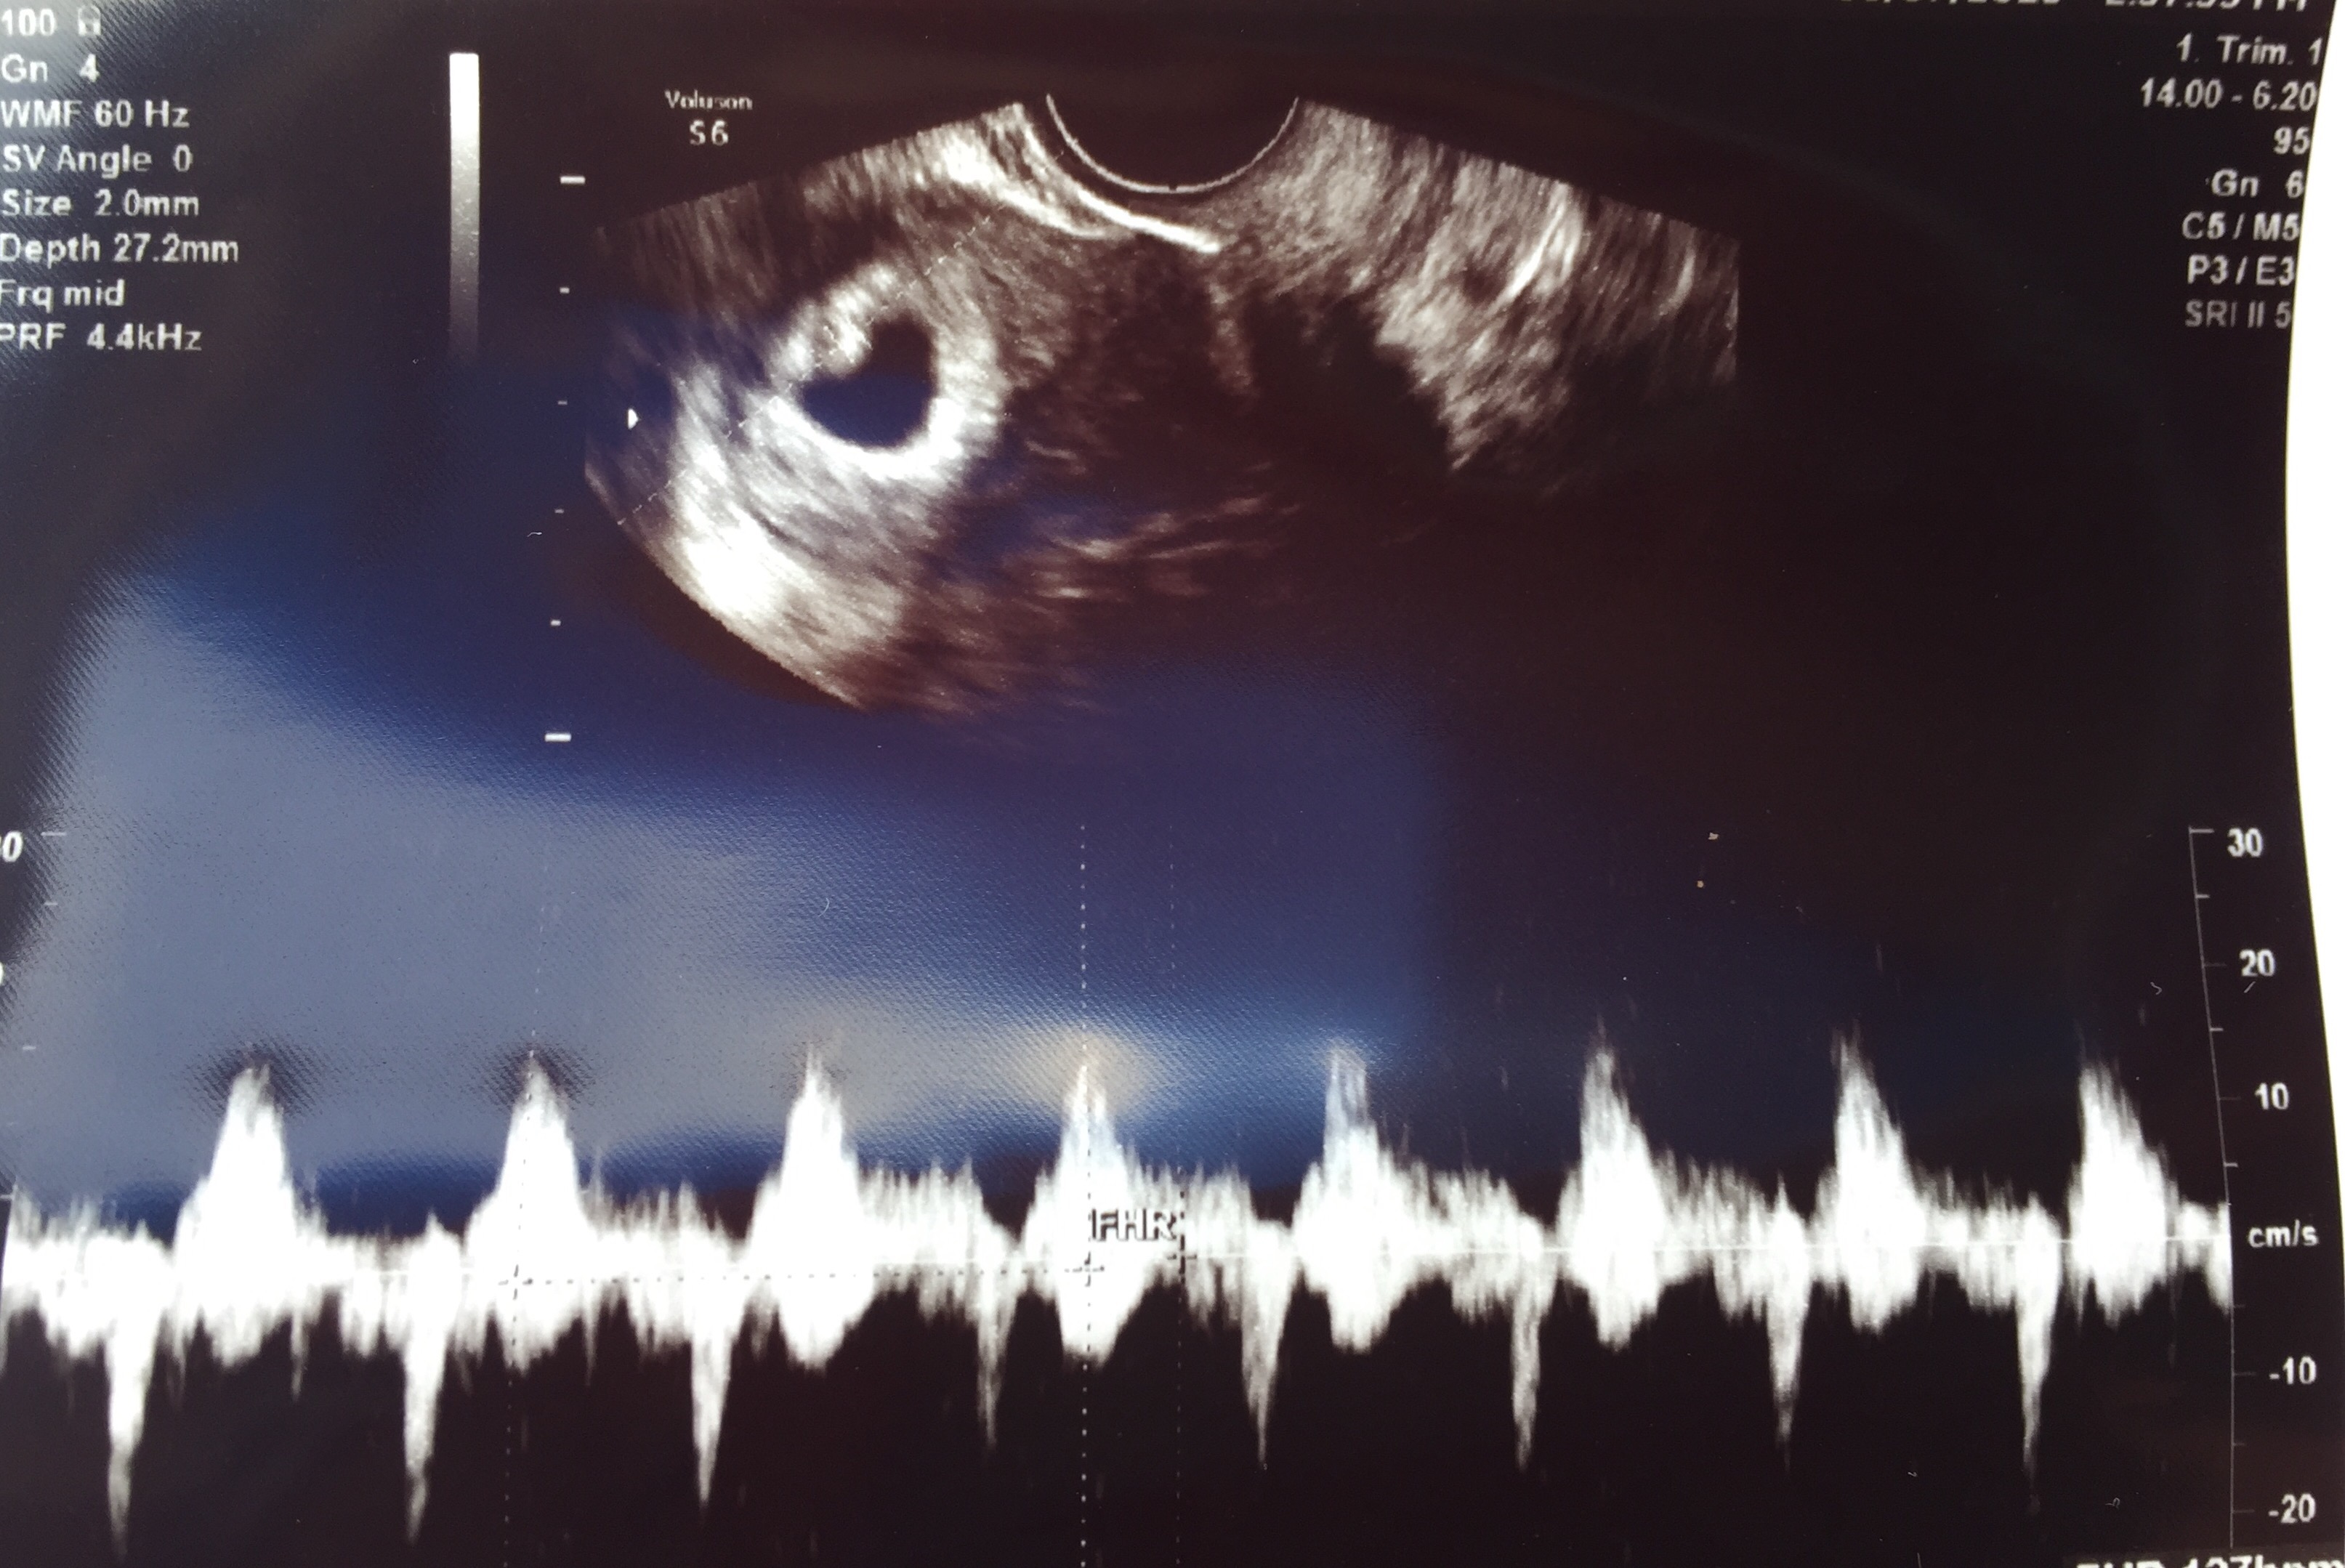

We did have a minor scare when we had our ultrasound. For a few seconds we couldn’t hear a heartbeat. Both our hearts dropped. Turns out the speakers were turned low and the heartbeat is very strong (171) but still – just makes you realize how vulnerable we still are. I asked my friend Terri “do you ever just not feel scared” and she said “nope, always a worry.” Just makes you think even more what a true and amazing miracle life really is.